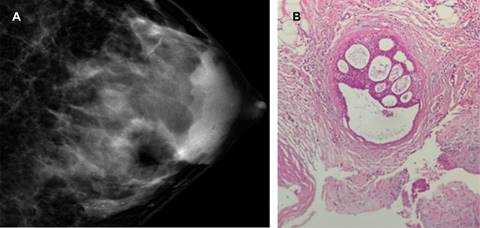

La hiperplasia ductal atípica ocurre dentro de las unidades lobulillares ductales terminales y aparece como una proliferación de células epiteliales monomórficas espaciadas uniformemente que tienen bordes celulares bien definidos y núcleos generalmente redondeados, en donde las células forman lúmenes secundarios y/o micropapilas perforadas (Figura 1).15

Figura 1: Hiperplasia ductal atípica. A) Mastografía en craneocaudal con calcificaciones agrupadas pleomórficas del cuadrante superoexterno. B) Resultado histopatológico con proliferación de células epiteliales monomórficas que dan el aspecto de micropapilas perforadas.